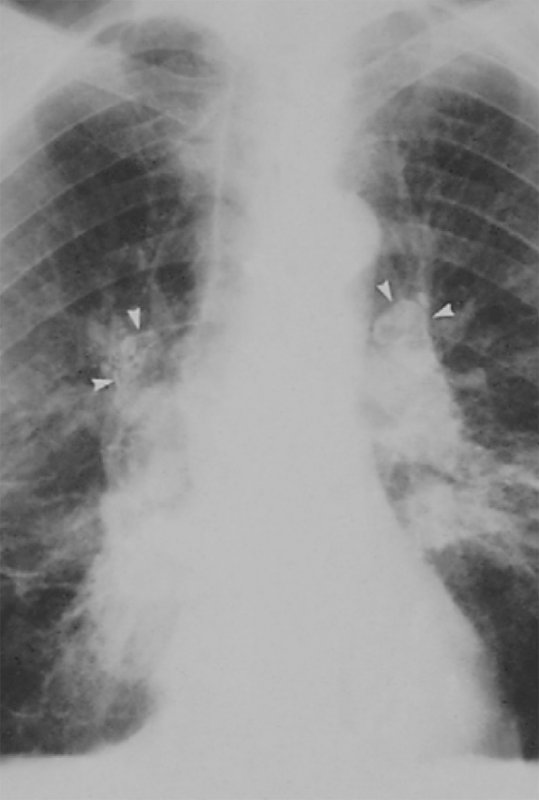

II стадия – в легких визуализируются множественные очаговые тени, размером от 5 до 10 мм – так называемая картина «снежной бури». Может определяться обызвествление узелков. Также отмечается выраженная деформация и усиление легочного рисунка с образованием ретикулярных теней (отметим, что на этом фоне сосудистый рисунок определяется плохо) (рисунок 1).

Рисунок 1. Силикоз (II стадия). В легких определяются множественные очаги обызвествления – картина «снежной бури»